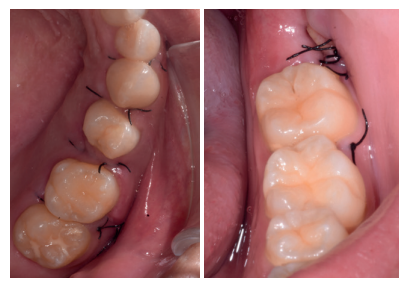

Los fragmentos coronal y radicular procedentes del tercer molar inferior y del premolar superior se limpiaron de restos de tejidos blandos y, secos, se introdujeron en la máquina Smart Dentin Grinder® (Kometa Bio, BIONER, España), tal y como aparece en la Figura 14. Tras un ciclo de triturado de 3 segundos, y otro de tamizado de 20 segundos, el material obtenido se limpió con la primera solución durante 12 minutos, y después durante 3 minutos con la segunda solución (Figura 15), para después transportar el material de injerto al alveolo, con presión controlada (Figura 16). Una vez compactado, se colocó una membrana de colágeno (Figura 17) y se suturó la herida con seda de 4/0, mediante puntos periodontales en las papilas (Figura 18). Se realizó una radiografía panorámica en el postoperatorio inmediato (Figura 19).

A los diez días se retiró la sutura (Figura 20), donde se puede observar una buena cicatrización de los tejidos blandos. A los 4 meses se realizó una revisión, clínica (Figura 21) y radiográfi ca, mediante radiografía panorámica (Figura 22) y un escáner de haz cónico (Figura 23), donde se puede apreciar la integración del material de injerto y una densidad ósea similar al hueso adyacente, derivando de nuevo a la paciente para comenzar el tratamiento ortodóntico.